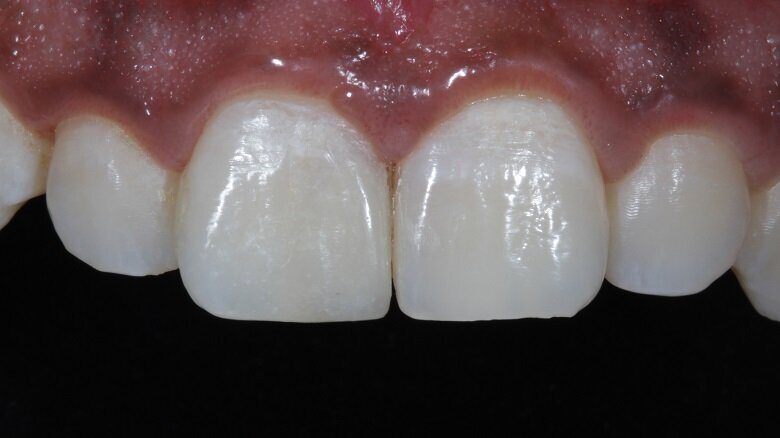

Fig 21: Final Post-Operative photograph

Discs and rubber cups were used for the final polishing protocol. Bilateral symmetry was then achieved (Fig 19). A lateral view of the teeth depicted the surface texture (Fig 20). The patient was then recalled after 48 hours for a check-up (Fig 21).